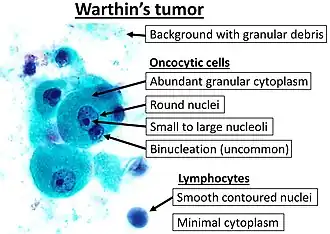

Oncocyte

An oncocyte is an epithelial cell characterized by an excessive number of mitochondria, resulting in an abundant acidophilic, granular cytoplasm. Oncocytes can be benign or malignant.

- Oncocytoma, a tumour composed of oncocytes, may be found as a less common salivary gland neoplasm also known as oxyphilic adenoma.

- Köybaşioğlu FF, Önal B, Han Ü, Adabağ A, Şahpaz A (2020). "Cytomorphological findings in diagnosis of Warthin tumor". Turk J Med Sci. 50 (1): 148–154. doi:10.3906/sag-1901-215. PMC 7080357. PMID 31769640.{{cite journal}}: CS1 maint: multiple names: authors list (link)

Binucleation:

- Dr.S. Malliga (2006-10-18). "A correlative cytological and histopathological study on lesions of salivary gland" (PDF).

- Chan MKM, McGuire LJ: Cytodiagnosis of Lesions Presenting as Salivary Gland Swellings: A Report of Seven Cases. Diagn Cytopathol 8: 439-443, 1992b. - ^ Image by Mikael Häggström, MD. Reference for findings: Carlos C. Diez Freire, M.D., Shahla Masood, M.D. "Apocrine metaplasia". Pathology Outlines.